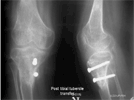

Management (2 stages):

1). Correction of angular deformity and limb length discrepancy by using Ilizarov Method

2). Reduction of patellar dislocation by transfer of tibial tubercle (Fulkerson technique)

Post

Op

Child at 8year age and walking well and will need 2nd lengthening later age